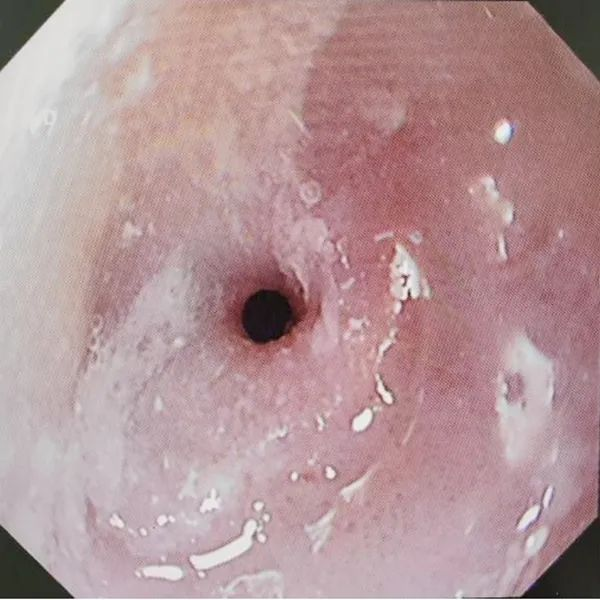

▲扩张前食管狭窄(约0.3-0.4cm)

两年前赖阿姨因腐蚀性食管炎造成食管狭窄,曾置入食管覆膜支架,但近期吞咽困难加重,吃流食也很难下咽,吃一顿稀饭需近一个小时,消化内科郑中文主任为该患者进行胃镜检查,发现进镜距门齿28-29厘米处食管腔呈环形向心性狭窄,直径仅约3-4毫米,内镜无法通过。经过综合评估,决定为其行内镜下球囊扩术。手术过程中,通过内镜活检钳道送入球囊扩张导管至狭窄段,注入生理盐水使球囊扩张,以4-8ATM(1ATM=101.325 kPa)的压力分次加压扩张,每次持续约1-2分钟,逐渐扩张狭窄食道。术后患者吞咽困难症状明显改善,无明显并发症表现,已于近日康复出院。